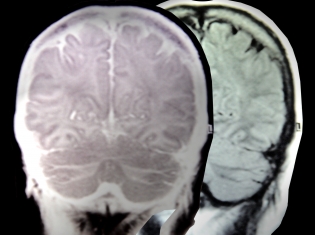

Alzheimer’s researchers create new antibody that enables detailed analysis of brain

A key distinctive sign of Alzheimer’s disease is the change in behavior of a protein called ‘tau.’ This protein is essential to neuron health and to the proper functioning of the brain.

In a normal brain, the tau protein exists as an individual. However, in a brain of someone with Alzheimer’s, the tau protein forms twisted structures called ‘neurofibrillary tangles.’ Kayed discovered a new intermediate structure that is even more damaging than the tangles.

The researchers developed a new antibody, called T22, that only bonds with these intermediate structures, called tau oligomers. This allowed them to analyze the prevalence of the structures in healthy brains and those with Alzheimer’s.